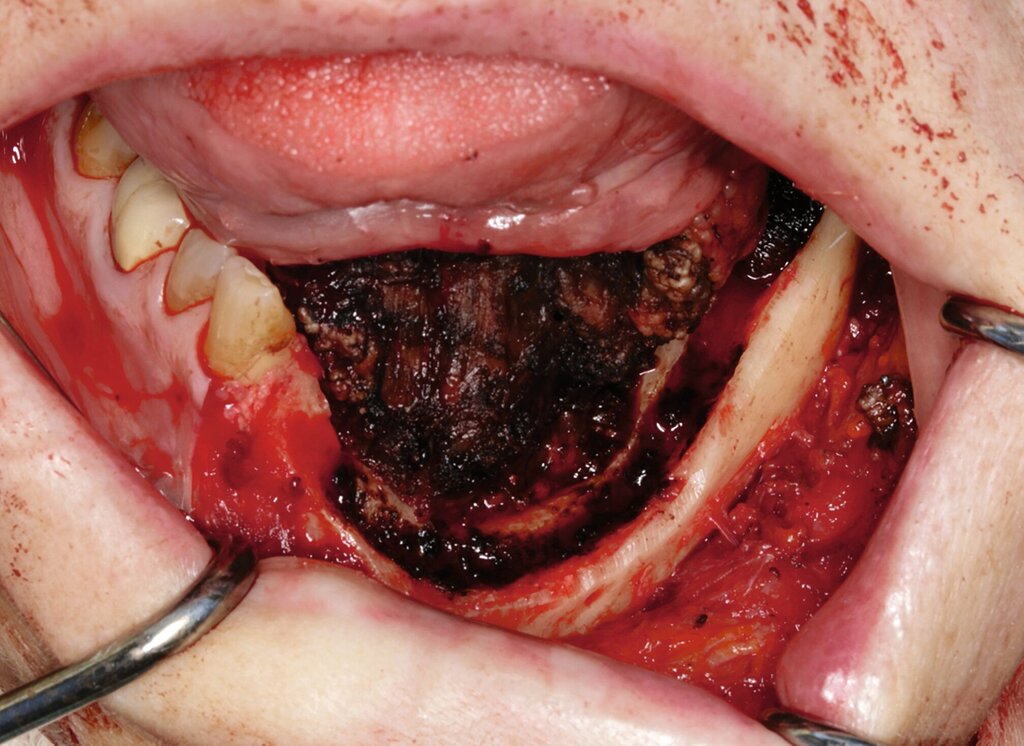

Eine im Januar 2024 alio loco durchgeführte Probenentnahme ergab eine resorptive Entzündung mit Pigmenteinlagerungen. Die Patientin berichtet, dass die Schleimhautveränderung etwa vier Wochen vor der Vorstellung bei uns begonnen habe zu wuchern. Klinisch zeigte sich eine 10 mm x 7 mm messende, exophytisch wachsende, schwarz pigmentierte Raumforderung (Abbildungen 1 und 2). Durch eine Probenentnahme in domo konnte histopathologisch ein malignes Melanom gesichert werden.

Die prätherapeutische Fallvorstellung im interdisziplinären Hauttumorboard ergab die Empfehlung zur primären Resektion und zu einer Halslymphknotenentfernung der Level I–III beidseits. Diese erfolgte im Sinne einer kontinuitätserhaltenden Unterkieferteilresektion (Abbildungen 4 bis 6). Die Rekonstruktion erfolgte durch ein mikrochirurgisch anastomosiertes, fasziokutanes Radialistransplantat vom linken Unterarm. Der Entnahmedefekt wurde mittels Vollhaut vom linken Unterarm gedeckt. Zudem wurde eine beidseitige selektive Halslymphknotenausräumung in Level IA, IB, IIA, IIB und III durchgeführt. Die Patientin konnte in gutem Allgemeinzustand am 15. postoperativen Tag entlassen werden.